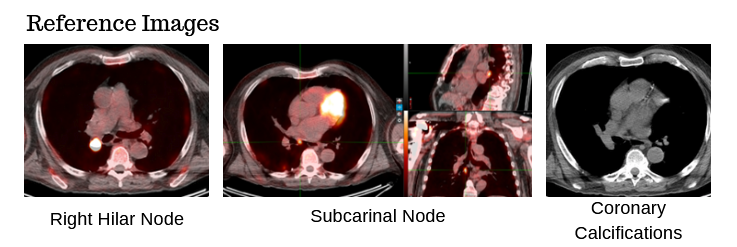

78-year-old male with a 30 pack-year history of smoking and previously diagnosed with Stage IIIA (T4 N0 M0) non-small cell lung carcinoma status post RUL/RLL bilobectomy two years ago and subsequently developed biopsy proven recurrence in right hilar and subcarinal lymph nodes. Definitive chemoradiation to 60 Gray with outback durvalumab is recommended after multi-disciplinary discussion.

The patient has no known history of cardiac disease, but the presence of coronary calcium is noted on the planning CT scans (4D-CT without contrast and free-breathing CT with contrast).

There is growing awareness of the impact of cardiac sub-structure radiation dose exposure on the risk of cardiac injury in lung cancer patients. Historically, the whole heart has been contoured, and the standard of care (such as NCCN guidelines) remains to constrain the whole heart (e.g. mean heart dose < 20 Gy) in the setting of definitive RT for lung cancer. Whole heart dose has been associated with survival (e.g. RTOG 0617), but a survival endpoint is multi-factorial and does not fully capture the cardiac impact of thoracic RT [1]. Emerging data suggests cardiac sub-structure radiation exposure may be more highly associated with specific cardiac toxicity events. For example, intermediate dose to the left-sided coronary arteries (e.g. V15) has been associated with the risk of coronary-related toxicity (e.g. major cardiovascular adverse events including MI, heart failure, coronary stenosis requiring intervention, and sudden cardiac death), while pulmonary vein dose has been associated with the risk of atrial fibrillation [2–5]. Thus, the ability to contour cardiac sub-structures at risk will be an important skill set for lung cancer RT moving forward.Faculty